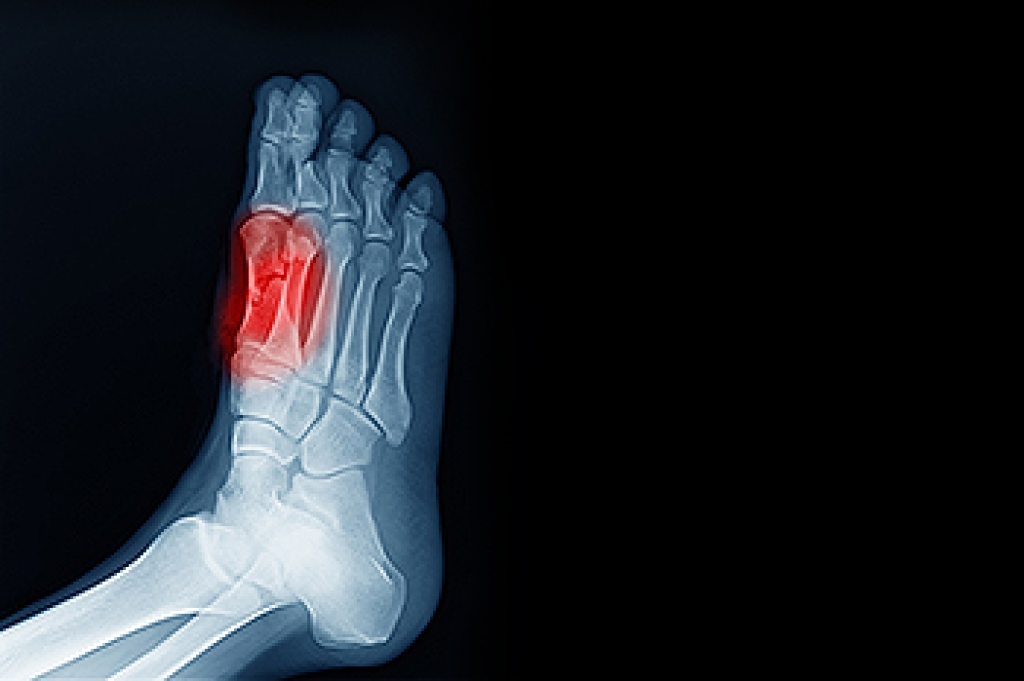

The most common injuries that occur in sporting activities include:

- Broken Foot

- Stress Fractures